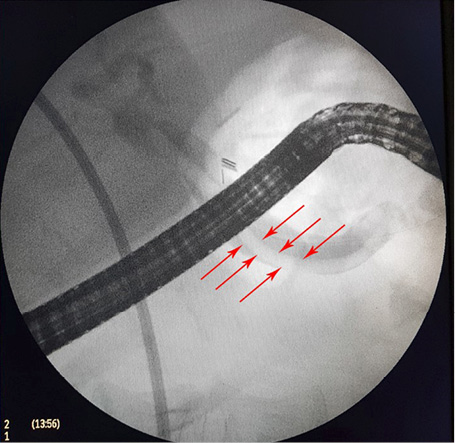

1 pav. Prisipildymo defektas (helmintas) BTL (pažymėta rodyklėmis), nesant echogeninio šešėlio

Atlikus ultragarsinį pilvo tyrimą, konstatuota, kad tulžies pūslė pašalinta, BTL 0,8–1,0 cm pločio. Jo spindyje pastebėtos hiperechogeniškos masės (0,6–0,8 cm skersmens), distaliniame gale susiliejančios į didesnes sankaupas (1, 2 pav.). Kitų vidaus organų ir struktūrų matomų patologinių pokyčių nenustatyta.

Sergant tulžies latakų askaridoze, kraujo tyrimai gali atitikti normos ribas. Tokiu atveju įtarti patologiją padeda paciento nusiskundimai, išsami ligos ir gyvenimo anamnezė (kelionės, namų aplinka, valgymo įpročiai ir sąlytis su dirvožemiu). Specifinių (ligą diagnozuojančių) laboratorinių tyrimų askaridozei nustatyti nėra. Tiksliai diagnozuoti parazitų invaziją į žarnyną, kai laboratoriniai tyrimai nepatologiniai, galima identifikavus askaridžių kiaušinėlius paciento išmatose [3, 27]. Kirmėlių migraciją į tulžies latakus galima nustatyti atlikus ultragarsinį tyrimą. Dažnai ultragarsu pastebimas prisipildymo defektas BTL. Jis būna pailgos arba cirkuliarios formos, be tulžies latakų akmenims būdingo šešėlio – artefakto. Dėl šios priežasties ultragarsu stebimas prisipildymo defektas dar vadinamas „minkštu“ radiniu (1, 2 pav.). Nors ultragarsinis tyrimas vertinamas kaip jautrus ir specifiškas (atitinkamai 40–70 proc. ir 90 proc.), tyrimo kokybė priklauso ir nuo tyrėjo patirties. Tulžies latakuose esant oro po buvusių intervencijų arba kirmėlių maceracijos metu, kai kirmėlė negyva, ji gali būti nepastebėta [2, 3].